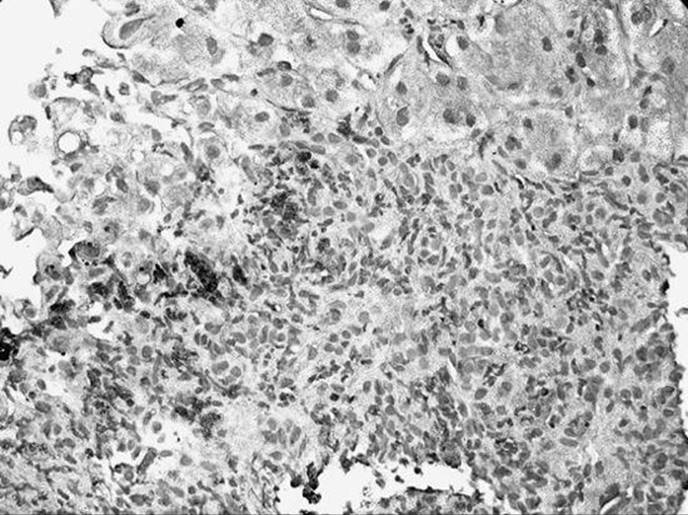

The liver biopsy specimen shown in the figure below is described in the pathology report as having nodular lymphocytic portal infiltrates, some with germinal centers. This is most suggestive of what type of viral hepatitis?

Figure 51-4

Hepatitis C. The presence of a portal area with a lymphoid aggregate or a follicle with a germinal center in a liver specimen with other features of chronic hepatitis is most suggestive of chronic hepatitis C. It should be noted that hepatitis C is notable for sometimes having some degree of bile duct involvement/injury. This can make the distinction between recurrent hepatitis C and allograft rejection difficult in some liver transplant biopsies.